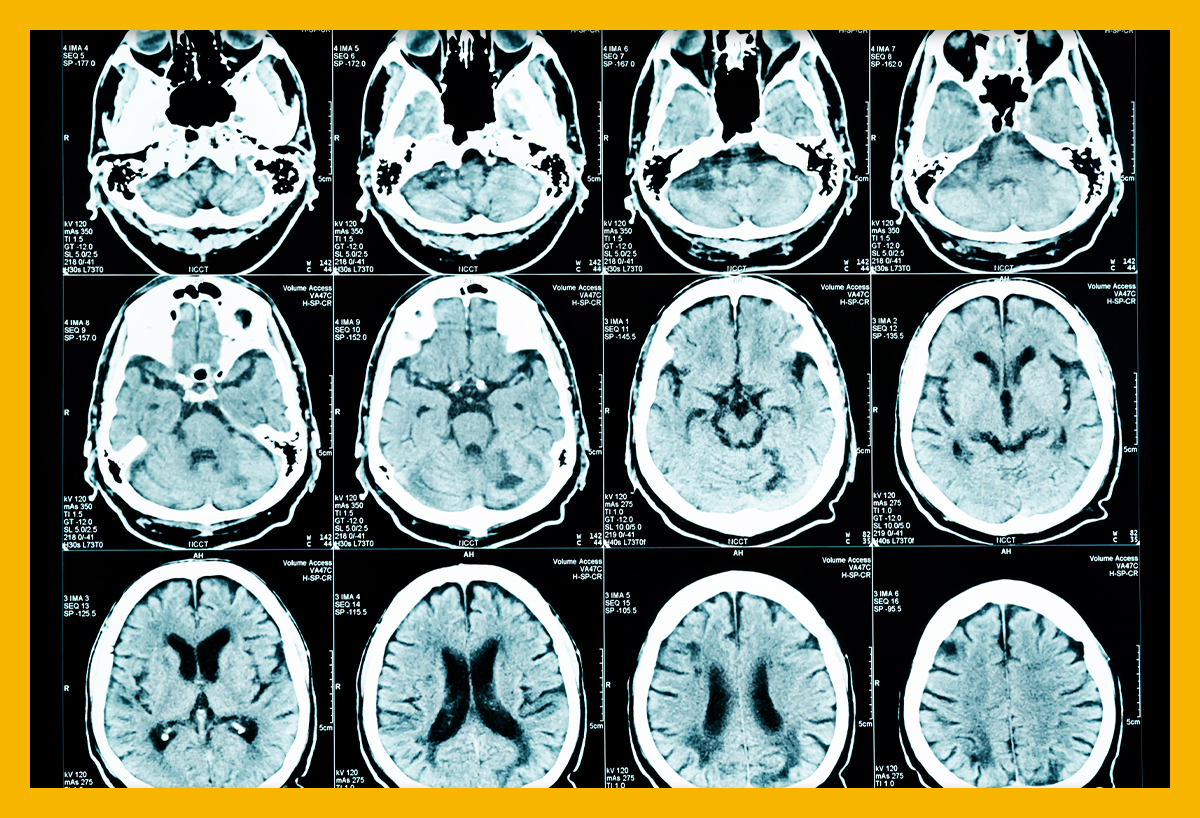

먼저 뇌경색이 뭔지 알아보겠습니다.뇌경색과 뇌출혈에 대해 궁금해하시는 분들이 많습니다.뇌혈관이 파열되어 피가 혈관의 포일로 새어 나간 경우가 뇌출혈입니다. 뇌출혈과 조금 다르게 뇌혈관 길이 막히는 게 뇌경색입니다.콜레스테롤 수치가 높은 분이라면 특히 혈관이 막히지 않도록 주의하시기 바랍니다.

첫 번째는 급성 뇌경색 발병 연대입니다.대부분 고령자에게 나타나는 증상이지만, 최근 현대인에게는 50대 이상부터 발병하는 경우도 많다고 합니다.뿐만 아니라 30대 젊고 건강한 신체를 가지고 계신 분들도 스트레스성으로 인한 급성 뇌경색 발병이 많습니다.

두 번째는 급성 뇌경색 증상입니다. 대표적인 증상으로는 두통입니다.대수롭지 않은 두통과 달리 심한 통증을 동반한다면 급성 뇌경색을 의심해봐야 합니다.두통과 함께 말이 부정확하고 섣불리 구사된다면 좀 더 주의해볼 필요가 있다.

한쪽 팔이나 다리가 마비되는 경우도 급성 뇌경색의 전조 증상 중 하나입니다.뇌경색은 동맥이 경화되기 때문에 의식불명이 되는 사례도 있습니다.뇌에 가까운 눈도 증상이 나타나는 경우가 많습니다.

눈 시력이 급격히 떨어지거나 시각적으로 장애가 생기면 뇌경색을 의심해봐야 합니다.이때 양쪽이 아닌 한쪽 눈이 흐려지거나 시야를 확보할 수 없다면 즉시 응급실이나 병원을 방문하는 것이 좋습니다.

술 취한 사람처럼 갈식하려고 걷거나 휘청거리는 경우도 급성 뇌경색을 의심해봐야 합니다.뇌 질환의 경우 제대로 걷기가 힘들고 걸을 때 마치 취한 사람처럼 비틀거리는 현상을 흔히 볼 수 있다고 합니다.다리가 저리거나 걸음걸이가 잘 안 되는 경우는 급성 뇌경색의 증상 중 하나입니다.